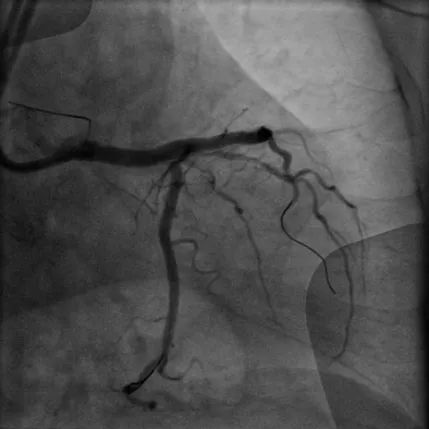

CTO病变:患者74岁男性,主因胸痛10余天,憋气1周余,加重2天入院,既往高血压、糖尿病病史、长期吸烟史。诊断急性非ST段抬高型心肌梗死、心力衰竭。强化用药改善心功能后择期行冠脉造影示LAD为CTO,RCA近段CTO病变、全程钙化影,圆锥支向LAD远端提供侧支循环。患者拒绝CABG治疗,决定开通RCA CTO。但患者RCA严重钙化,GW在微导管支持下通过CTO段,但应用普通球囊预扩后,无法送入IVUS导管,遂果断选择GuideZilla支持下Shockwave冲击波球囊治疗,成功植入支架,手术效果良好,为进一步解决LAD病变奠定了基础。